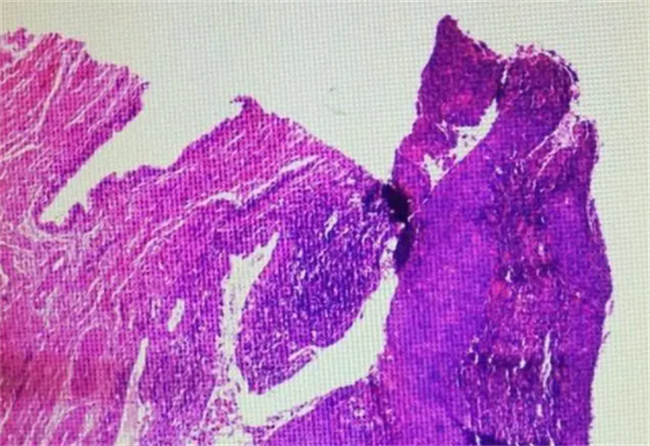

宫颈原位癌是一种早期的宫颈癌,它通常在宫颈上皮内发生,并未扩散到周围组织。由于宫颈原位癌早期症状不明显,很多女性可能会忽略其存在,但是及早发现和治疗宫颈原位癌是可以治愈的。

包括手术、冷冻治疗、放疗和激光治疗等。手术是治疗宫颈原位癌的一种常见方法,它可以通过切除宫颈病变部位来达到治疗的效果。冷冻治疗是将液氮直接喷洒在宫颈病变部位上,冻结并杀死癌细胞,达到治疗效果。放疗和激光治疗也可以杀死癌细胞,治疗宫颈原位癌。但需要注意的是,这些治疗方法可能会对患者的身体产生一定的副作用,如不适、疼痛等。在治疗宫颈原位癌时,患者需要密切关注自己的身体状况,注意治疗后的恢复期。在术后恢复期间,应该避免性生活和重物提拿等活动,以免对手术部位产生牵拉和撕裂。同时,也需要按照医生的建议和指导,按时服用药物和进行康复训练,促进伤口愈合和身体恢复。

宫颈原位癌是可以治愈的

但是治愈的前提是早期发现和治疗。因此,女性应该定期进行妇科检查,以便及早发现和治疗宫颈原位癌。如果发现宫颈有异常,如阴道出血、白带异常等症状,应该及时就医,进行全面的身体检查和治疗。另外,预防宫颈原位癌的发生也非常重要。女性可以通过预防HPV感染、避免过度疲劳和感染等方式来减少宫颈原位癌的发生风险。同时,保持身体健康,注意个人卫生和清洁等因素也可以预防宫颈原位癌的发生。

宫颈原位癌是一种早期的宫颈癌,早期发现和治疗可以完全治愈。治疗方法包括手术、冷冻治疗、放疗和激光治疗等,但需要注意的是这些治疗方法可能会对患者的身体产生一定的副作用。因此,在治疗期间,患者需要密切关注自己的身体状况,遵守医生的建议和指导,按时服药和进行康复训练,促进伤口愈合和身体恢复。